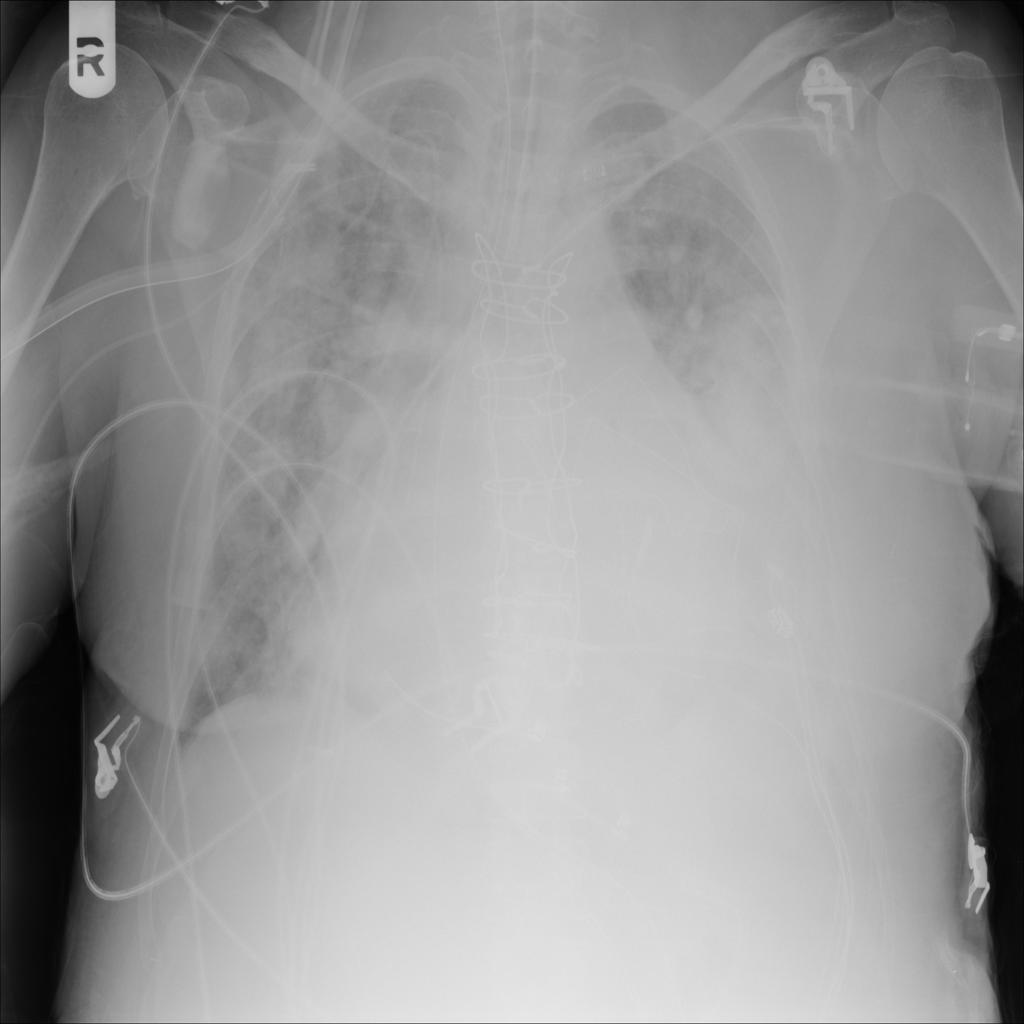

PAT-3384 · IMG-000Cardiomegaly

PAT-3384 · IMG-000

AP